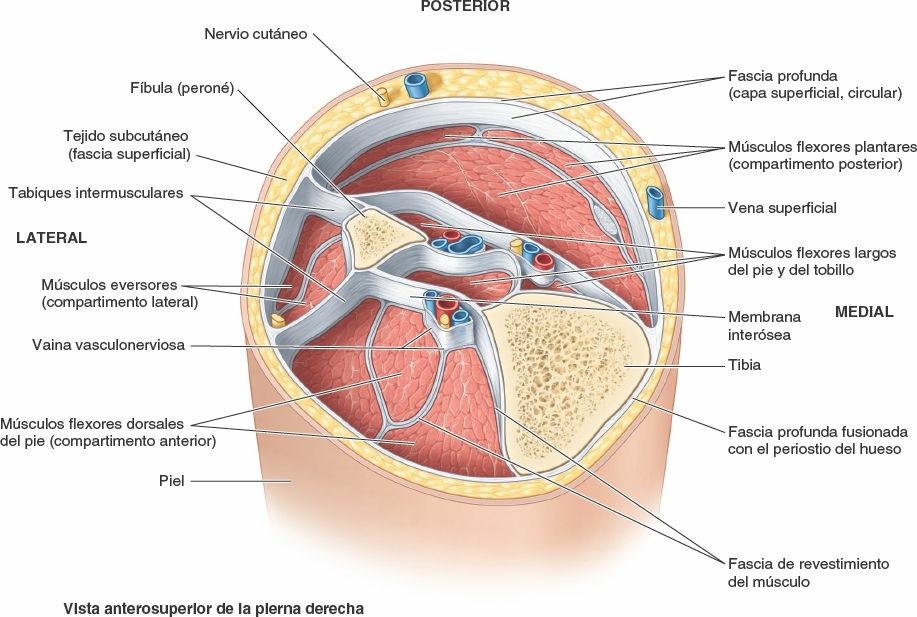

De forma breve podemos decir que la piel está formada por 3 capas:

1-Epidermis o barrera protectora donde encontramos la melanina.

2-Dermis, en ella se hallan los vasos sanguíneos, linfáticos, terminaciones nerviosas y está formada por colágeno y elastina, que le dan consistencia y elasticidad.

3-Tejido subcutáneo, hipodermis o también llamada FASCIA SUPERFICIAL. Esta capa está mayoritariamente formada por grasa que se encarga de mantener la temperatura corporal y protegernos de los daños ocasionados por impactos.

La FASCIA SUPERFICIAL se une a la piel y a la FASCIA PROFUNDA a través de unas fibrillas diagonales y perpendiculares rodeadas de tejido graso en su mayoría. Y a su vez, la fascia muscular profunda se une al músculo a través del epimisio (capa de tejido conjuntivo que rodea al músculo).

Este mecanismo se produce gracias a la conexión entre los tejidos y a la propiedad elástica del vendaje neuromuscular, el cual genera una tracción y transmisión de dicha tracción desde la primera capa de la piel hasta la fascia profunda, epimisio y músculo. Esta tracción transmitida generará la activación de receptores locales y activación del mecanismo reflejo de defensa que intentarán mantener el estado de reposo, obligando a las capas profundas a moverse en el mismo sentido de la tracción que genera el vendaje neuromuscular.

Dicho de otro modo, la capa superficial de la piel se mantiene en estiramiento constante por la tracción del VENDAJE NEUROMUSCULAR y para conseguir una posición de reposo, la capa profunda, debe deslizarse en la misma dirección. El organismo buscará la relajación de las fibras que conectan las diferentes capas.

Hay que tener en cuenta que el tejido subcutáneo o fascia superficial comparte inervación con el músculo en la zona que limitan ambos con la fascia profunda, así que cuando se provoca un estímulo de deslizamiento entre el tejido subcutáneo y la fascia, estaremos provocando un estímulo sobre el músculo para contraerse o relajarse.